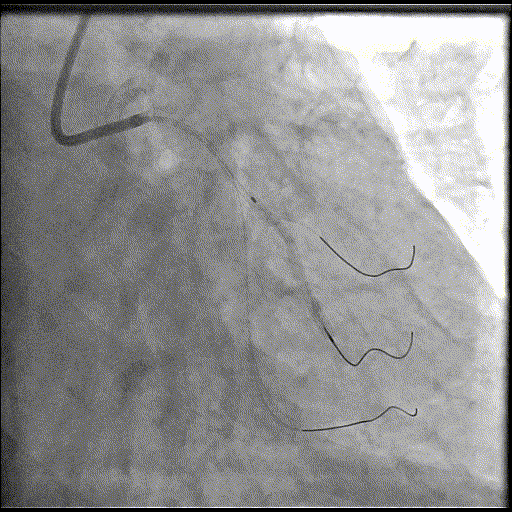

于LM-LAD依次植入两枚药物洗脱支架,经非顺应性球囊后扩张支架,复查造影&IVUS提示血管内钙化仍较重,支架贴壁不良,遂再次启动IVL治疗。

再次冲击波球囊治疗

3.0*12mm@4atm 冠脉血管内冲击波导管反复进行5个周期治疗,并选取后扩张球囊对病变行扩张治疗。最终复查造影提示残余狭窄小于10%,未见夹层及血肿,TIMI血流3级。